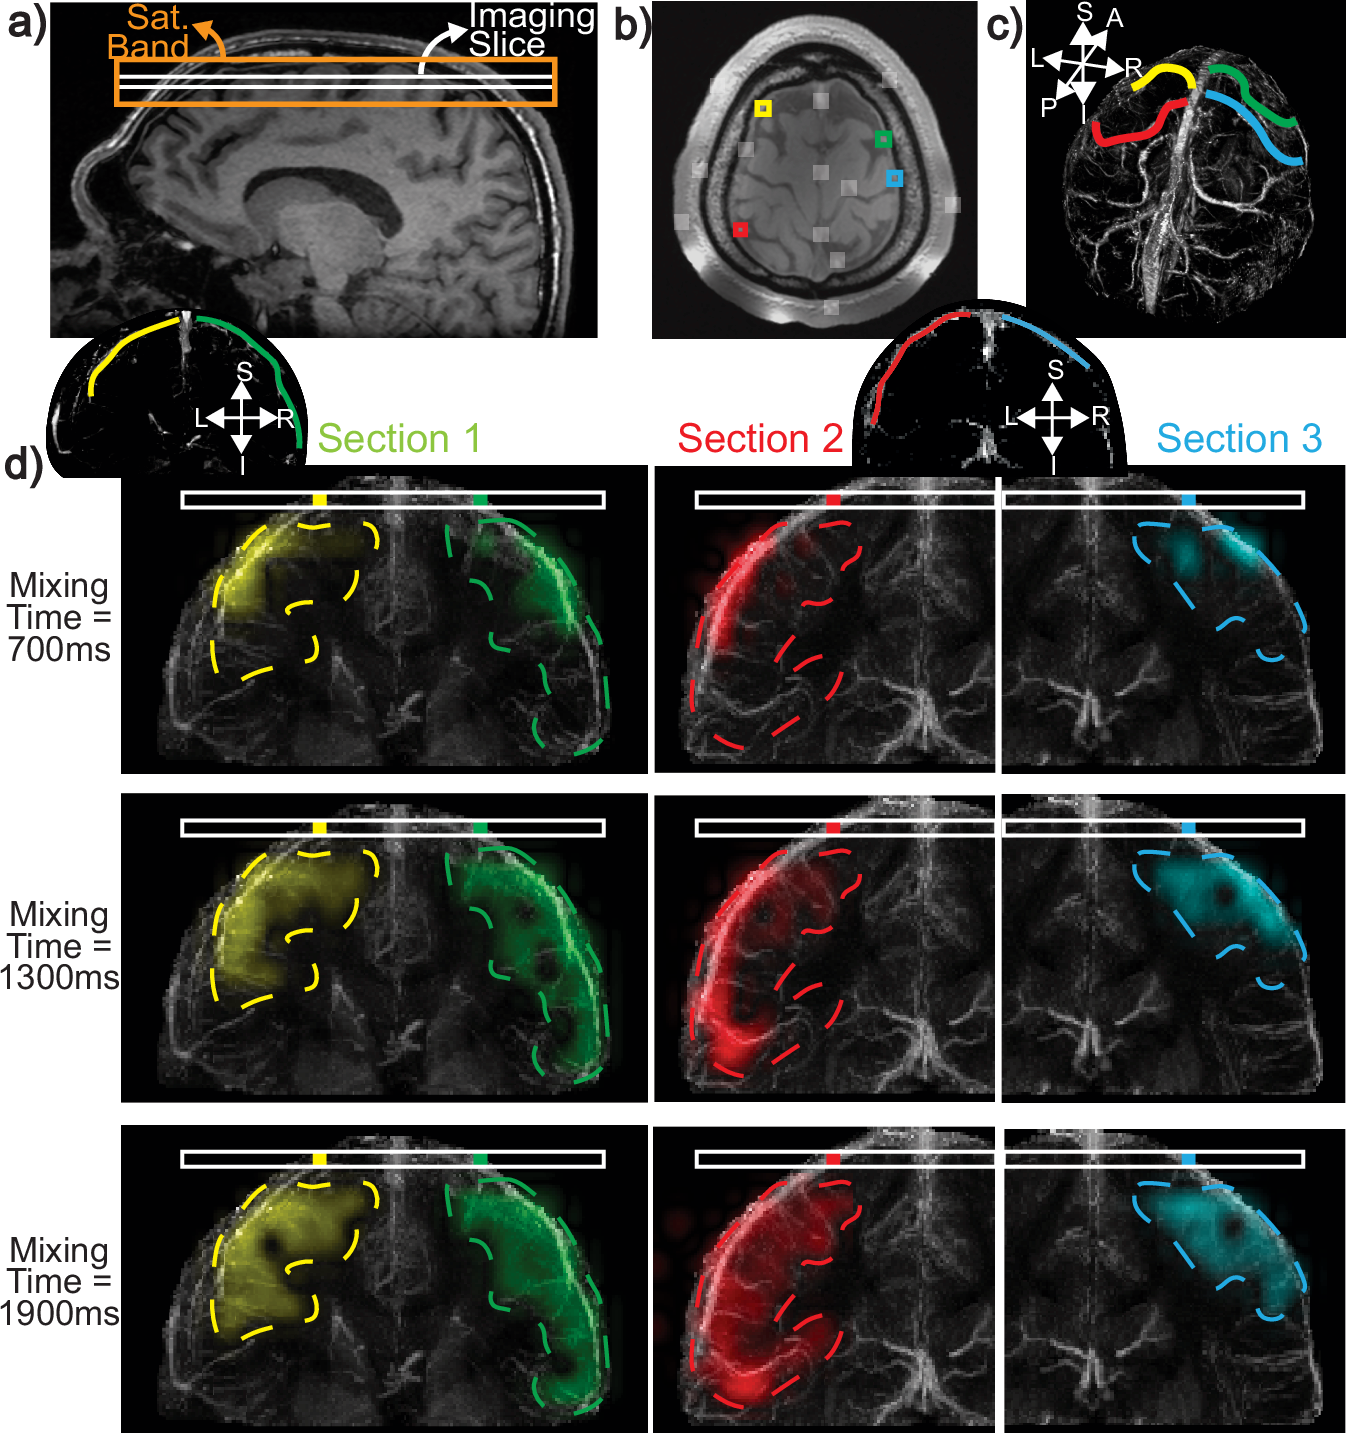

Fig. 3: Setup and results for perfusion source mapping of individual superior veins.

a A sagittal image showing the placement of the axial imaging slice and saturation band. b From the dataset, different vessels that flow through the imaging slice can be identified by examining the perfusion source map energy of target image voxels and detecting peaks. The detected peaks are overlaid with white ROIs on the image. Four color-coded ROIs are selected out of these regions, each containing a different superior vein that drains into the slice. c The color-coded draining veins overlaid on a 3D Quantitative Susceptibility Mapping (QSM) venogram. Anatomical orientations for the QSM-venogram are labeled as follows: Anterior (A), Posterior (P), Superior (S), Inferior (I), Left (L), and Right (R). d 2D perfusion maps from each ROI, overlaid on the coronal sections of QSM-venograms, showing the ability to trace the sources of blood. Over short mixing times, blood remains in the large vein. For longer times, the diffused maps indicate blood coming from smaller veins and potentially from capillary beds and surrounding tissue. The coronal projection of the venous territory, obtained from the perfusion source maps, is shown with dashed contours for each vein. Source data are provided in ref. 54.